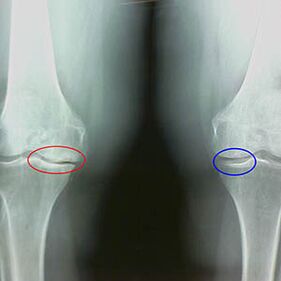

X-rays determine the degree of joint occurrenceRevealing the pathological processes involved in bone structure.Their changes indicate that the muscle system has been imbalanced for 5-10 years.Usually, peopleFor several years, they have been suffering.

The second stage of the joint is considered easy.X-rays showed obvious bone spurs, but the cartilage was not affected.The amount of synovial fluid has decreased, but there are symptoms of pain after walking and running for a long time, stiffness during bending, and pain in knee positions.

Early X-ray characteristics of the second stage of the knee joint:

- The tip edge of the tip nodule on the tibia, with cruciate ligaments attached;

- The medial joint space becomes narrower;

- The medial bone has a less transverse edge - depending on the development of extroversion or variable joint deformation.

Stage 2 in LarsonMore than 50% of the stenosis of joint space is characteristic, but this can only be checked by different dynamics or comparisons from the joints.

X-rays showed the presence of bone plants, which was a change in the space between the femur and tibial bones, indicating that the knee lost cartilage.Sometimes, X-rays from the knee joint show significant signs of cartilage wear, but the patient has no obvious pain.On the contrary, jointness in the first stage can disrupt the function of the knee, due to the pain, the bass muscles.